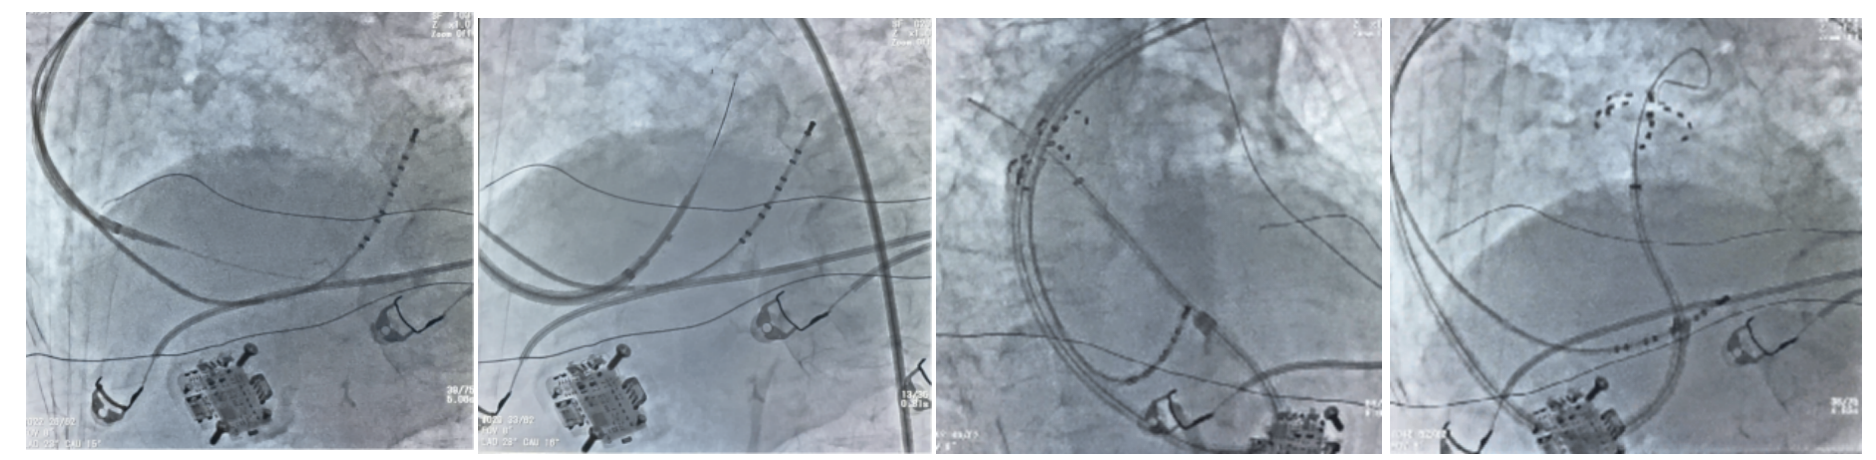

术中造影显示患者下腔静脉极度迂曲,无法经常规途径送入导管。团队及时调整手术路径,改为左腋静脉入路,采用 AccuSafe 穿刺导丝联合 Navigo 8.5Fr 可调弯鞘完成房间隔穿刺,并运用医院首创 Y 阀造影剂显影方法确认进入左房。术中依托可调弯鞘与导丝双重安全保护机制,避免误穿与组织损伤,精准完成穿间隔操作。随后送入 Farapulse PFA 导管,完成双侧肺静脉及上腔静脉消融隔离,累计放电 37 次,电位完全阻断,手术顺利成功。

图 5 左 1 左 2 为房间隔穿刺过程;右 1 肺右上肺静脉花瓣状消融;右 2:左上肺静脉网篮状消融